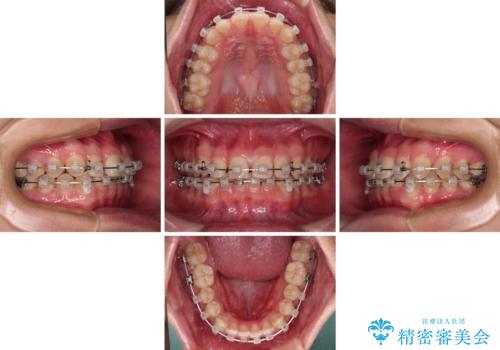

隙間とデコボコを治したい ワイヤー装置による矯正治療

- クリアブラケット

- 前歯のデコボコと隙間を気にして来院された患者様です。

治療手段としてはワイヤー装置でもインビザラインでも可能でしたが、インビザラインの自己管理は自信がないとのことで、ワイヤー矯正により隙間を閉じていくこととしました。

隙間の原因は舌の突出癖であったので、舌癖改善のためのトレーニングを指導しながら治療を進めて行くこととしました。

舌の突出癖がなかなか改善されず、治療開始時よりも隙間が大きく開いてしまう時期がありましたが、最終的にしっかりと閉じて終了することができました。